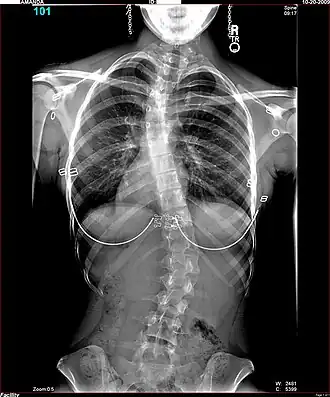

Men onderscheidt een S-vormige scoliose met twee bochten en een C-vormige scoliose met één bocht. Een S-scoliose benoemt men naar de convexe (bolle) kant van de grootste bocht; bijvoorbeeld een S-vormige thoracale scoliose, rechts convex van 35 graden. De wervelkolom is meestal tevens om zijn as gedraaid, men spreekt dan van een torsiescoliose, waardoor een bochel (gibbus) ontstaat. Hoewel het een ingewikkelde driedimensionale vervorming betreft, kan men op een gewone voor-achterwaartse röntgenfoto de zijdelingse verkromming goed zien als een C-vormige of een S-vormige slinger in de ruggengraat die eigenlijk een rechte lijn behoort te zijn. Een structurele scoliose zal meestal gepaard gaan met een draaiing, een torsie; ook een bijkomende voorovergebogen houding (kyfose), een holle rug (lordose) of beide komen vaak samen met de scoliose voor. Belangrijk is of de scoliose in evenwicht is, dat wil zeggen of het zwaartepunt van het lichaam tussen de voeten valt. Als de wervelkolom van de patiënt een S-vormige bocht heeft, kan zich op borsthoogte een convexe bocht naar rechts bevinden en op lendenniveau een convexe bocht naar links. Meestal heffen de bochten elkaar op. Indien dit niet het geval is, bestaat er een grote kans op verergering.

Klachten